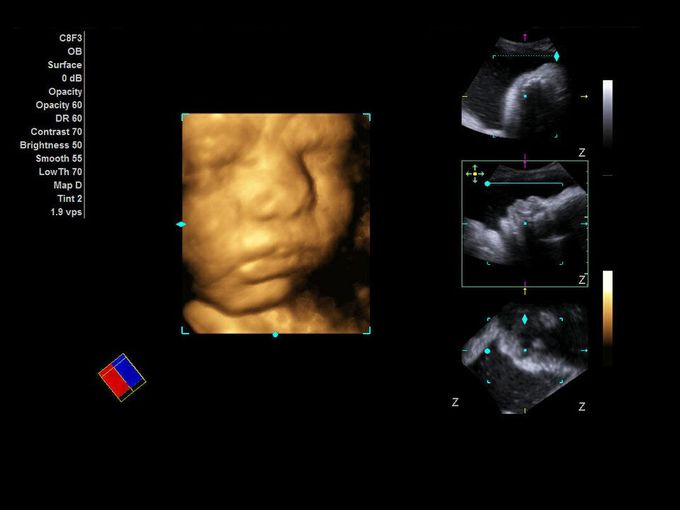

Кроме новой техники, можно заказать восстановленные медицинские системы: ультразвуковые сканеры, томографы, флюороскопы, ангиографы и хирургические установки С-дуга.